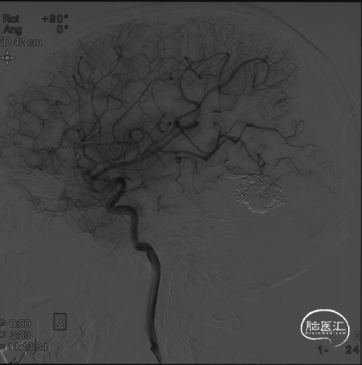

2023-10-13左侧颈内动脉正侧位造影,可见畸形团部分再通,主要位于原畸形团的后外侧,左侧大脑中动脉颞后分支向畸形团供血,且通过细小皮层静脉向横窦引流,引流静脉不通畅

畸形团大小:1.6cm×1.3cm

由左侧大脑中动脉、颈外动脉分支(脑膜中动脉和枕动脉)参与供血

通过皮层静脉向横窦引流

畸形团分布集中,位于非功能区

Spetzler-Martin I级,Buffalo III级

3D显示大脑中动脉两分支、MMA和OA各有一支为畸形团供血,其中大脑中动脉和OA分支均较细,MMA是主要的供血动脉,畸形团小,引流静脉起始部清晰,预计可以经动脉入路完全栓塞。但由于残留畸形团相对分散,经一支供血动脉完全弥散至整个畸形团可能较难,遂决定行经动脉入路”高压锅“技术治愈性栓塞,促进栓塞材料在畸形团的弥散,另外,为了避免栓塞不全引起的出血并发症,先栓塞来自大脑中动脉的供血动脉